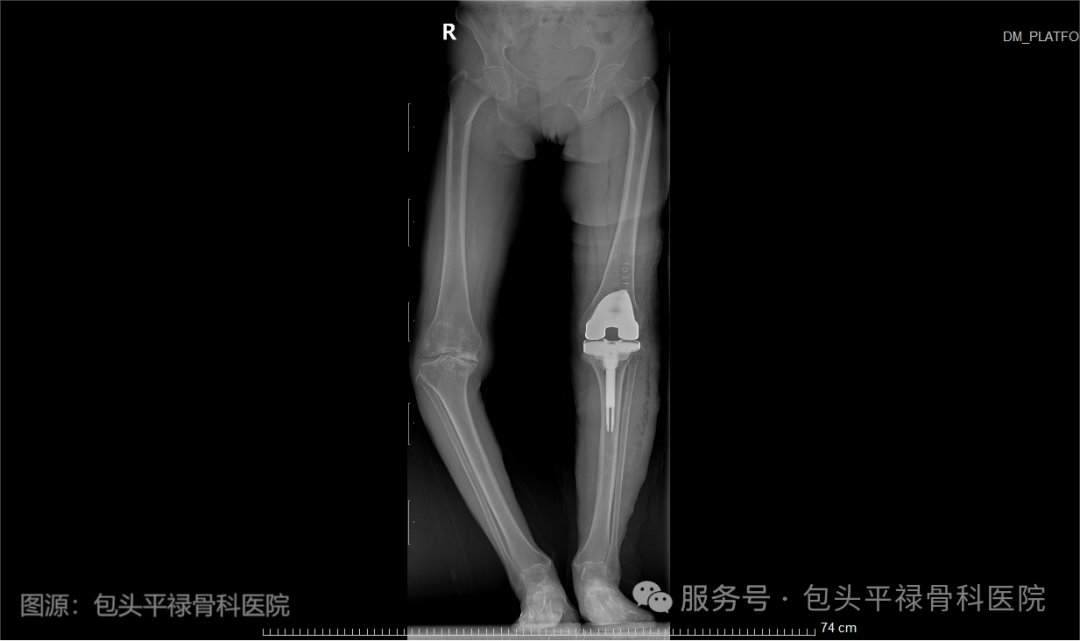

老年患者左膝术前VS康复治疗仪VS患者术后复查